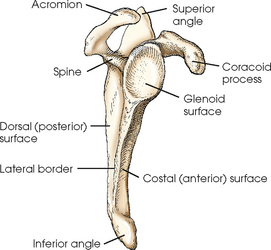

What kind of bone is the scapula classified as?

flat bone

Explain the location of the scapula

What is the anterior surface of the scapula called?

costal surface (comes in contact with the ribs)

What is the posterior surface of the scapula called?

dorsal surface

The scapular spine/crest divides the dorsal surface of the scapula into what 2 portions?

infraspinous/infraspinatus fossa

supraspinous/supraspinatus fossa

What is another term for the medial border of the scapula?

vertebral border

What is another term for the lateral border of the scapula?

axillary border

Which border of the scapula is thicker, medial or lateral?

lateral

What makes up the superior angle of the scapula?

junction of superior and medial borders

What makes up the inferior angle of the scapula?

junction of medial and lateral borders

What vertebrae does the inferior angle of the scapula correspond with?

T7

What is located at the lateral angle of the scapula?

head (glenoid) and neck of scapula

What is the coracoid process of the scapula?

fingerlike process extending anteriorly from the scapular notch

What is the acromion process of the scapula?

posterior flattened oval process at the lateral end of the scapular spine

What is the scapular notch?

prominent indentation along the superior border of the scapula

What is the glenoid fossa?

the head/neck of the scapula (point where humeral head articulates with scapula to form the scapulohumeral/glenohumeral joint)

Label the scapula (and determine whether it is a right or left)

Label the scapula